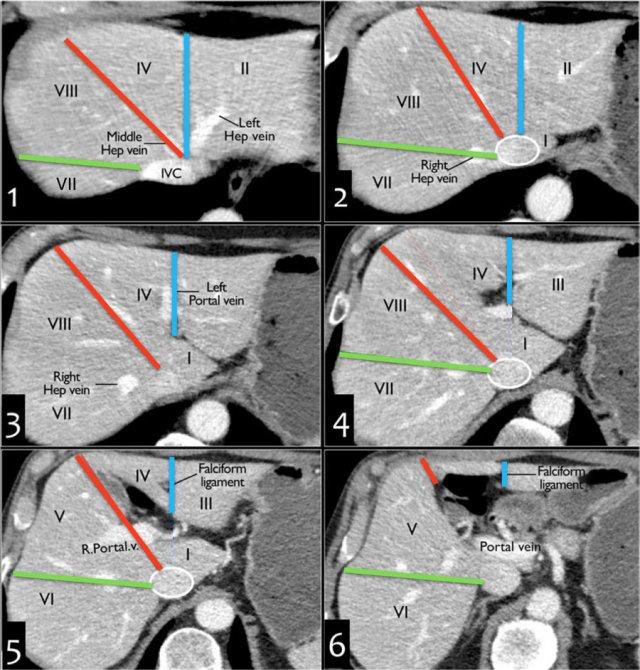

Giải phẫu trên mặt cắt ngang

Hình này là mặt cắt ngang qua các phân thùy gan trên, được phân chia bởi tĩnh mạch gan phải, tĩnh mạch gan giữa và dây chằng liềm.

Đây là mặt cắt ngang tại mức tĩnh mạch cửa trái.

Ở mức này, tĩnh mạch cửa trái chia thùy gan trái thành các phân thùy trên (II và IVa) và các phân thùy dưới (III và IVb).

Tĩnh mạch cửa trái nằm ở mức cao hơn so với tĩnh mạch cửa phải.

Hình ảnh này ở mức tĩnh mạch cửa phải.

Ở mức này, tĩnh mạch cửa phải chia thùy gan phải thành các phân thùy trên (VII và VIII) và các phân thùy dưới (V và VI).

Mức của tĩnh mạch cửa phải thấp hơn so với mức của tĩnh mạch cửa trái.

Tại mức tĩnh mạch lách, nằm thấp hơn mức tĩnh mạch cửa phải, chỉ có thể quan sát được các phân thùy dưới.

Cách phân biệt các phân thùy gan trên hình ảnh cắt lớp

Gan trái: phân thùy ngoài (II/III) so với phân thùy trong (IVA/B)

Kéo dài một đường dọc theo dây chằng liềm lên trên đến chỗ hợp lưu của tĩnh mạch gan trái và tĩnh mạch gan giữa tại tĩnh mạch chủ dưới (đường màu xanh lam).

Gan trái so với gan phải: IVA/B so với V/VIII

Kéo dài một đường từ hố túi mật lên trên dọc theo tĩnh mạch gan giữa đến tĩnh mạch chủ dưới (đường màu đỏ).

Gan phải: phân thùy trước (V/VIII) so với phân thùy sau (VI/VII)

Kéo dài một đường dọc theo tĩnh mạch gan phải từ tĩnh mạch chủ dưới xuống dưới đến bờ ngoài gan (đường màu xanh lá).